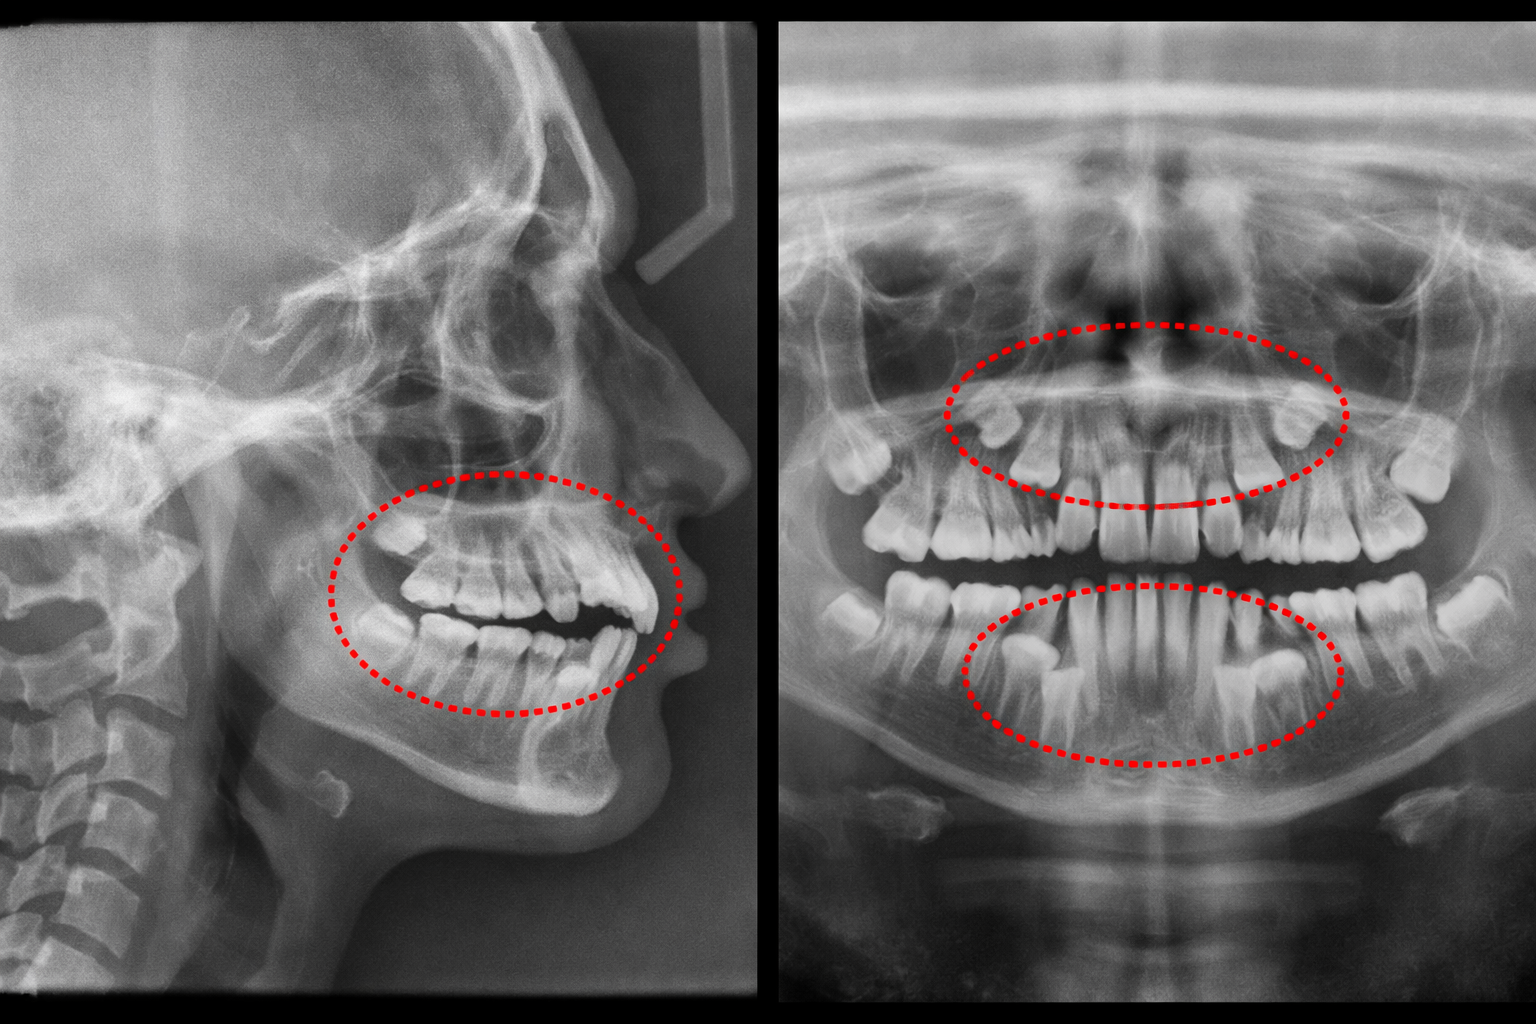

•レントゲン撮影(顎や歯の根の状態を見る)

これらの検査によって、

•歯はどの方向に動かせるのか

•動かして問題が出ないか

•抜歯が必要かどうか

•どの装置が適しているか

•どのくらい期間がかかりそうか

といったことを判断します。